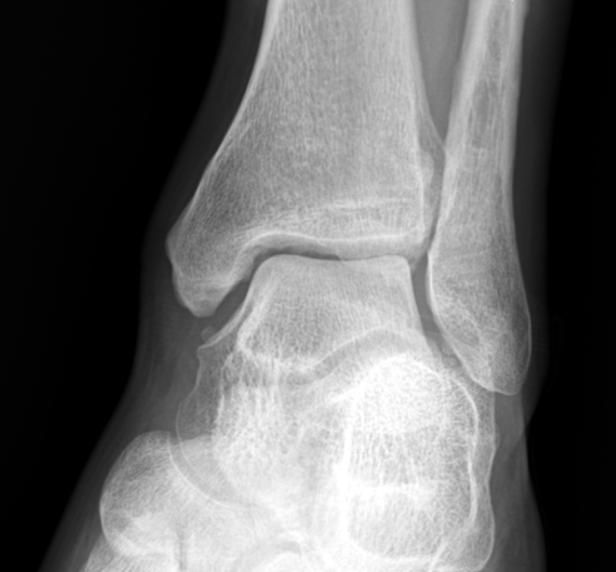

최근 발목이 아파 병원에 방문했더니 발목 관절염 초기라고 이야기해서

엑스레이 확인 후 자료 받아와 확인 해봤는데 저는 잘모르겠어서....ㅠㅠㅠ

병원 3군데 갔는데 2군데는 맞다 한군데는 애매하다는 소견을 내려주셨습니다.

혹시 엑스레이 사진상 발목 관절염이 확인 되는지 질의 드립니다.

만약 확인 되면 발목 관절염 현재 몇단계 정도 진행중인가요?

• 1번 째 사진

엑스레이상에서는 양쪽의 비교를 해보시는 것이 가장 정확하지만, 여러 의견을 들으신 것처럼 발목관절염의 초기로 보이지만, 관절에는 큰 변화가 없는 것으로 보이는데요

• 안녕하세요. 남희성 의사입니다.

애매하다고 표현하신 경우에도 다른 의사들이 관절염이 있다고 이야기하셔서 애매하다고 표현하셨지 골관절염이 아니라고 판단하셨을겁니다.

제가 보기에는 관절염 소견이 보이지 않습니다.

만약에 관절염이 맞다고 하더라도 가장 초기단계로 생각하시면 되겠습니다.